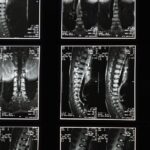

L’objectif principal de la décompression neurovertébrale est d’atténuer la douleur et de promouvoir la guérison des structures vertébrales. Il est essentiel d’identifier les besoins spécifiques de chaque patient afin d’adapter la thérapie. Cela implique une évaluation initiale approfondie, incluant l’analyse des antécédents médicaux et des résultats d’imagerie.

Les avancées technologiques jouent un rôle crucial dans l’évolution de la décompression neurovertébrale. L’intégration d’outils de diagnostic, tels que l’imagerie par résonance magnétique, permet d’évaluer plus précisément les besoins des patients. Les dispositifs modernes, dotés de fonctionnalités avancées, offrent des traitements personnalisés qui améliorent les résultats cliniques.

Au cœur de cette méthode se trouve une compréhension profonde de l’anatomie et de la physiologie de la colonne vertébrale. Le Dr. Desforges souligne l’importance d’évaluer chaque patient individuellement pour déterminer l’approche thérapeutique la plus appropriée. Grâce à l’intégration d’outils technologiques avancés tels que des dispositifs de décompression assistée par ordinateur et des systèmes de suivi numérique, les praticiens peuvent personnaliser les traitements pour maximiser les résultats cliniques.